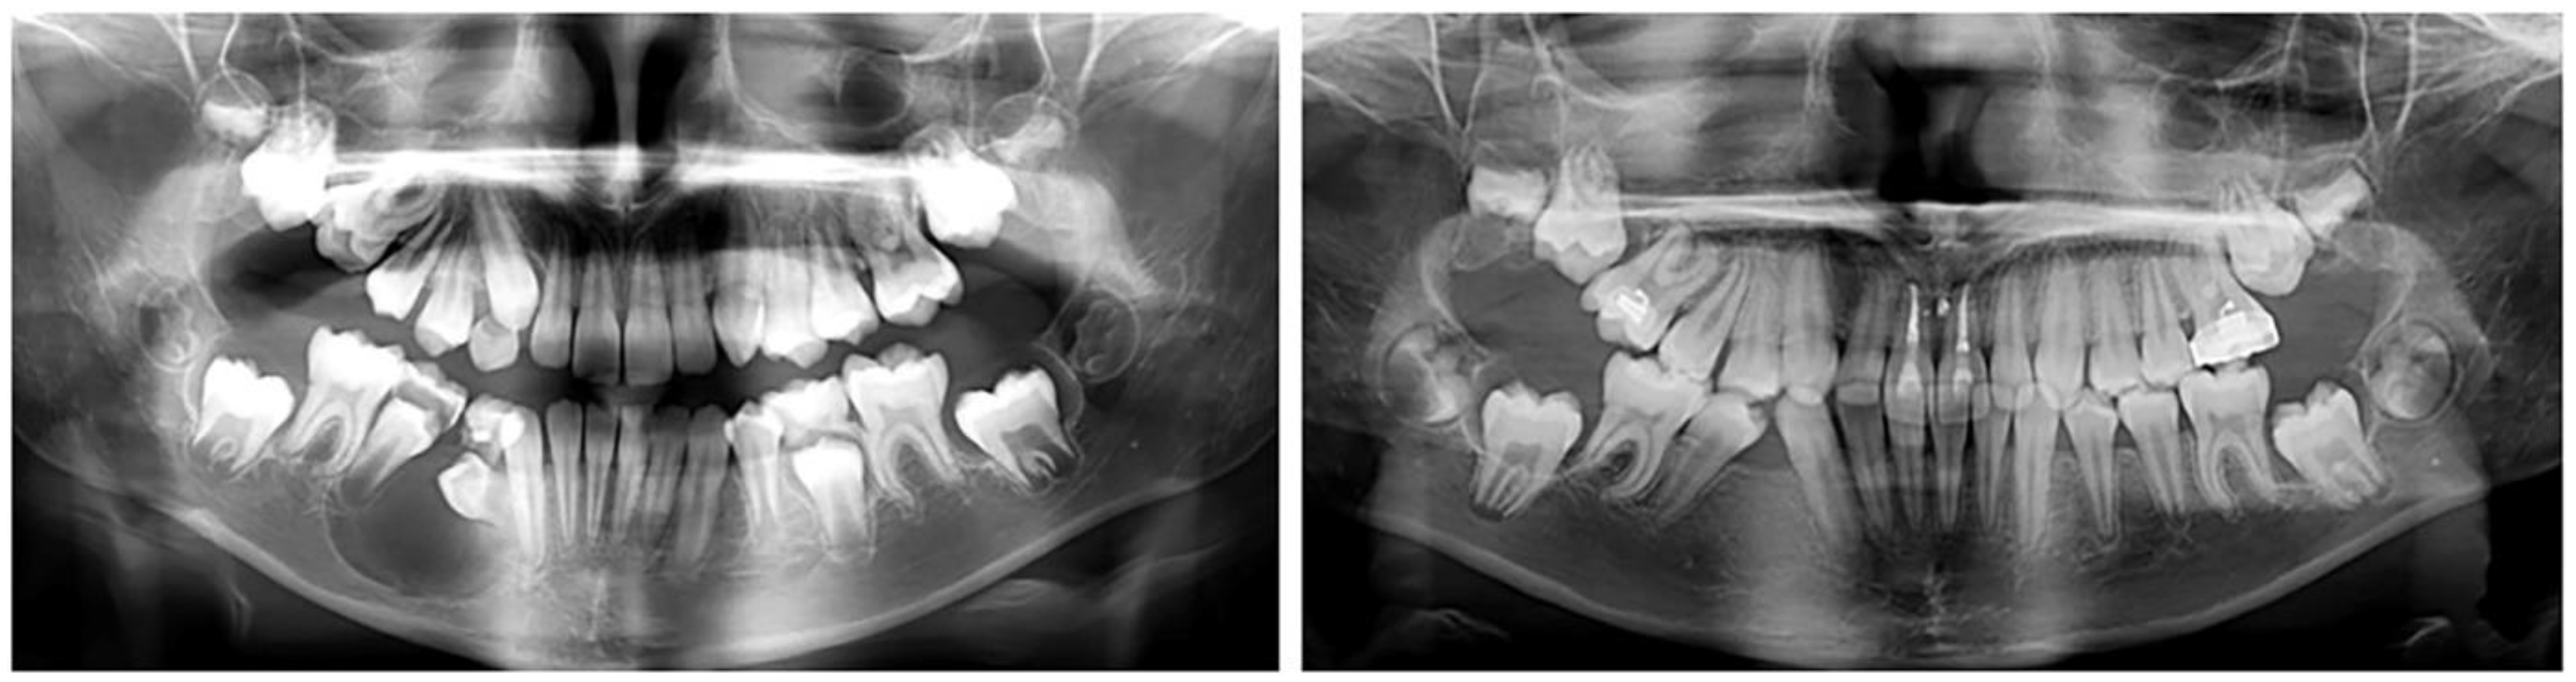

2.2.2. Clinical Case 2–Impaction of Upper-Right First Molar

The second case involved a 10-year-old girl sent for orthodontic treatment by a maxillofacial surgeon. A cystic lesion involving teeth 44 and 45 was detected, operated on and tooth 44 was extracted. A follicle cyst was detected in the upper dental arch around tooth 16, which changed the direction of development of the germ of the upper-right first molar (Figure 3). The molar was impacted with the crown in vestibular direction. Its orthodontic traction was recommended. For this, it was necessary to construct an anchorage area in the palate. The characteristics of the bone did not allow for the use of mini-implants. Therefore, the plan involved a PDaA, which included the premolars on both sides and the left first molar, as well as part of the hard palate. In the second clinical case, a wider palatal part was used, which engaged the hard palate in the support system. The purpose of this solution is the maximum support for rotational and extrusive movement of the upper-right first molar. During treatment, the patient suffered trauma, and the alveolar bone in the upper-central incisors was fractured. The stable distal segment was a good decision in this case. In the area of tooth 16, a “ladder” was designed with a series of hooks for attaching the elastic chain. The grid was printed from Co-Cr metal.

Figure 3. Oral status and CBCT examination of a patient with cystic lesions in the upper and lower jaw. Upper-right first molar was impacted with changed direction of crown position.

Figure 5. Change in the position of the upper-right first molar and the restoration of the alveolar bone in the lower jaw.